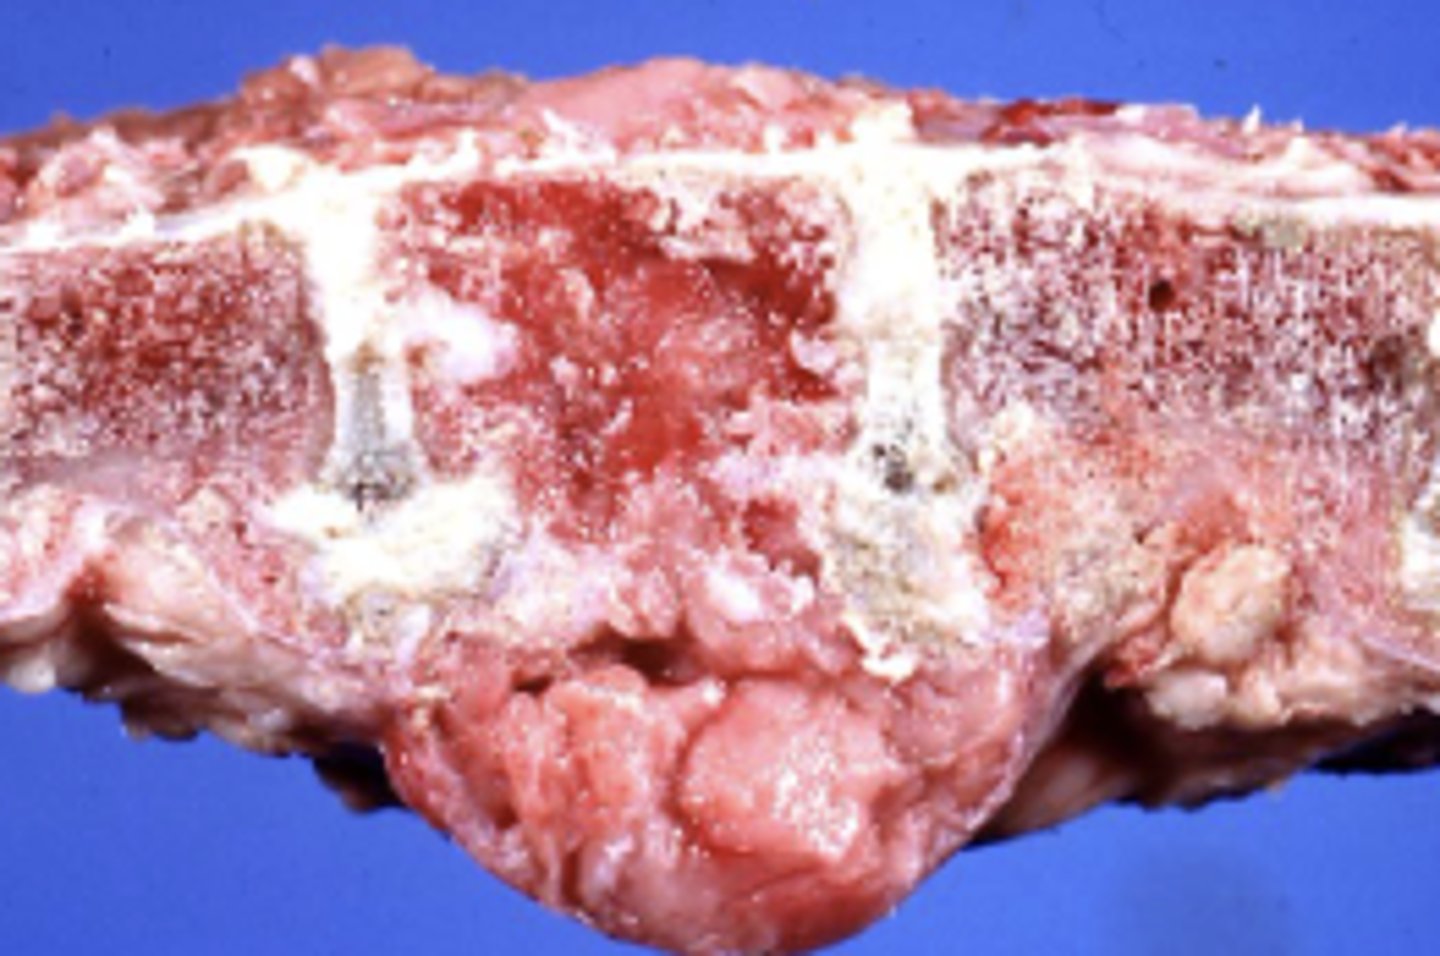

Hypertrophic Osteopathy

-due to periosteal new bone growth on the long bones

What kind of tumor is this? (broad category)